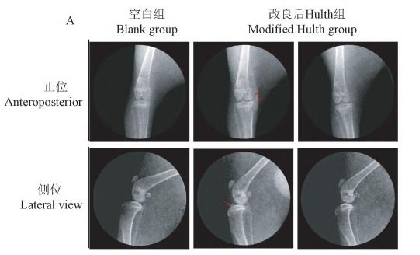

影像学和解剖学分析:

改良后 Hulth 法构建的 KOA 模型主要表现为骨赘生成、股骨髁部软骨脱落和大量软骨细胞克隆形成,软骨损伤程度更为严重;

关节腔注射胶原酶诱导的 KOA 模型主要表现为软骨表面缺损,胫骨平台软骨基质丢失和炎性因子升高,相比于改良后的 Hulth 法更为简便,创伤性小,更接近人的 KOA 进程与发病机制。